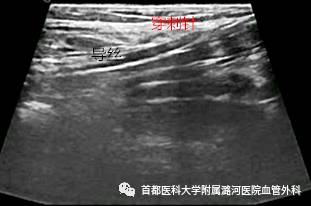

彩色多普勒超声

左侧髂静脉受压处管腔变扁,前后径变小。受压的远端扩张,呈“喇叭口”状改变。常伴髂静脉腔内血栓形成,长期血栓可形成大量侧支循环。

直接征像:

受压狭窄区域呈“五彩镶嵌”持续性高速血流;严重受压时受压处血流可缓慢,通过挤压肢体远端可见血流通过;完全闭塞时彩色血流信号中断。

间接征像:

受压远心端侧支循环形成,如髂内静脉血流反向,盆腔内静脉曲张等;髂外静脉呼吸相减弱,甚至消失。

正常髂静脉超声

注意事项

1. 因左下肢肿胀就诊的患者,如果下肢静脉无异常,应注意有无髂静脉受压。

2. 由于髂总静脉位置较深,一部分患者(特别是肥胖者)可能因肠气干扰显示不清。

3. 对该病的检查不能用力过重,以免造成人为的受压。

4. 超声不能显示管腔内的粘连带。